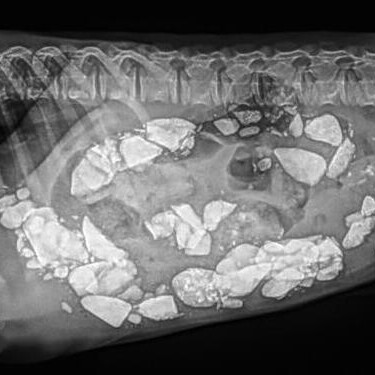

X-rays revealed a stomach full of rocks. Yes, rocks.

Over several days, vets kept an eye on the dog and it turned out, she was pooping out the rocks. So, no surgery was required.